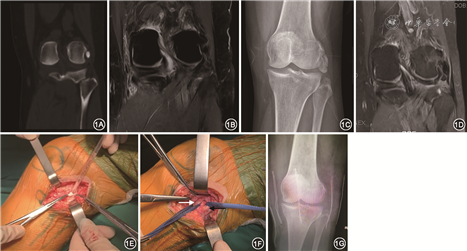

患者 女性,57岁,因“左膝关节疼痛4年余,加重4个月”于2020年9月14日入院。4年前患者无明显诱因出现轻度左膝关节疼痛,活动时加重,无发热等不适。于我院门诊就诊,行左膝关节CT、MRI检查(2016年5月),结果提示左膝外侧副韧带损伤,股骨外侧髁钙化灶,左膝退行性骨关节病(图1A、1B)。考虑诊断为“左膝外侧副韧带损伤”,予左膝制动、口服非甾体类抗炎药治疗后,疼痛缓解,后未行复查。4个月前患者无明显诱因出现左膝疼痛加重,伴“交锁感”,再次于我院门诊就诊。行左膝X线及MRI检查(2020年8月),结果提示左膝股骨外侧髁旁钙化灶较前明显增大,左膝外侧副韧带损伤,内侧半月板2度损伤(图1C、1D)。予镇痛、中医理疗、休息等保守治疗3月余,效果不佳。后为进一步治疗收住我科。体检:生命体征平稳,左膝关节无明显肿胀、畸形,左侧股骨外侧髁压痛明显,左膝屈伸活动度0°~90°,活动时疼痛加重,0°及30°内外翻试验阴性,肢端血供可,无感觉减退。实验室检查:血常规、生化检查、超敏C反应蛋白等指标均未见异常。入院诊断:左膝钙化性腘肌腱炎。

考虑患者经保守治疗效果不佳,钙化灶较前明显增大,建议行手术治疗;由于患者的钙化灶位于外侧副韧带和腘肌腱之间,为避免损伤关节囊,遂决定行开放手术,故于2020年9月15日在全身麻醉下行“左膝钙化灶清除术”。患者取仰卧位,患肢使用止血带,取以左膝外侧髁关节远端为中心的纵行切口,长约4 cm;逐层分离皮下组织,纵行切开阔筋膜,在外侧副韧带前方切开钙化灶,可见大量牙膏样乳白色物质流出(图1E),取少量周围组织送病理学检查;彻底清除钙化灶后可见腘肌腱位于深面,关节囊完整(图1F),术中使用C形臂X线机透视确定钙化灶完全清除后,冲洗创面,逐层缝合。病理学检查结果提示左膝滑膜组织严重伴钙化。术后复查左膝X线片,未见钙化灶残留(图1G)。术后患者左膝疼痛缓解,指导其进行早期康复锻炼,术后2周恢复正常活动。